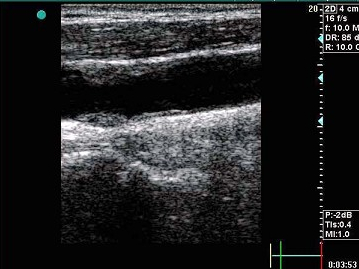

82、判断题

如图,颈动脉壁上异常光团提示动脉壁粥样斑块硬斑形成。